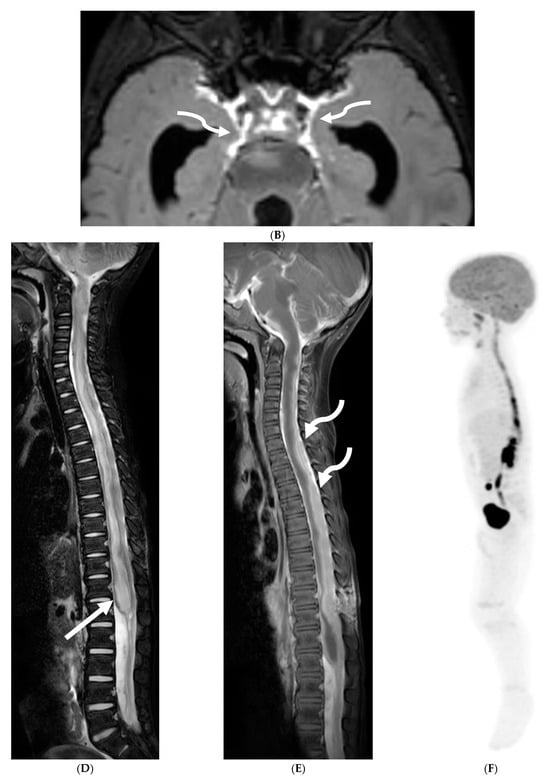

Figure 7.

3-year-old boy with 2 weeks history of headache and vomiting. Axial FLAIR (A), post contrast axial T1 FS (B) and sagittal 3D inversion recovery (C) images demonstrate FLAIR hyperintensity in the interpedencular cistern (curved arrow) and mild hydrocephalus. Extensive meningeal enhancement most prominent at the skull base, basal cisterns, and Sylvain fissures (arrows), but extending throughout the brain. There is meningeal enhancement, with coating of the brainstem extends inferiorly along the cervical spinal cord (dashed arrows). Sagittal T2 (D), sagittal T1 (E) and fat saturated T1 post (F) images show extensive leptomeningeal with predominantly solid and some cystic nodules (curved arrows) on T2 sequence and isointense on T1 (arrows). Lesions predominantly involve the posterior spinal canal, causing mass effect and anterior displacement of the spinal cord. The solid nodules show enhancement after contrast injection and extensive uniform diffuse LME around the cord (dashed arrows). Pathology: Primary Meningeal Rhabdomyosarcoma.